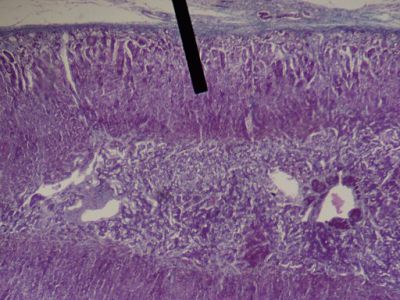

This is a histology slide of the adrenal gland. The pointer is on the zona fasiculata of the adrenal cortex.

Image by Jpogi, via Wikimedia Commons. Public domain.

No changes were made to the original image downloaded (note: this version was downloaded at reduced resolution from Wikimedia Commons).